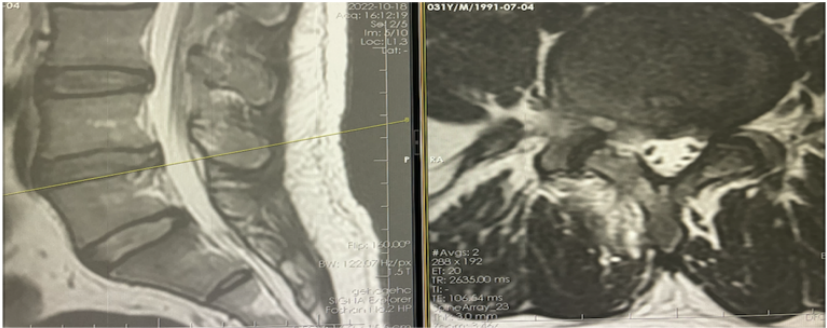

近两个月,他感觉右下肢疼痛及麻木症状较前严重了,以大腿后侧,小腿后外侧,足背及足底为主,行走及站立时感觉症状明显,卧床也不能有效改善,就去做了磁共振,结果一看:腰5/骶1右侧后方椎间盘突出,硬膜囊及右侧神经根受压。(虽然痛得比以前厉害了,但感觉还能再拖一拖)

随后,他就来到了佛山市第二人民医院骨二科,完善了术前腰推CT显示:腰5/骶1 椎间盘向右后方脱出,合并椎管狭窄,呈轻度钙化。

根据目前的症状体征和检查结果,诊断考虑为:1.马尾综合征,2.腰椎间盘突出症伴神经根病(L5/S1)。